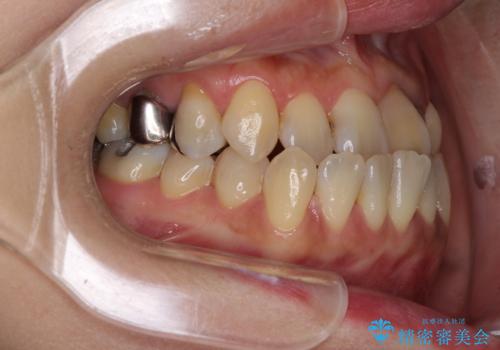

- 前歯の反対咬合により、日々強い痛みを感じているとのことで来院された患者様です。

骨格的に下顎が前方位にありますが、歯列矯正で前歯の被蓋関係を改善することができると判断されたため、インビザラインにより矯正治療を行うこととしました。

また、上顎前歯と下顎大臼歯に神経を取り除いた歯があったため、矯正治療後に、セラミッククラウンにて補綴することとしました。

前歯が内側に倒れ込む力がかかり、正常な歯ぎしりもできないため、非常に負担のかかりやすい咬み合わせでした。

矯正治療中に上顎前歯が下顎前歯を乗り越える際は、前歯でしか咬めない状況が続くため、食事など不便を感じましたが、治療後には前歯の痛みもなくなり、安定した咬み合わせとなりました。